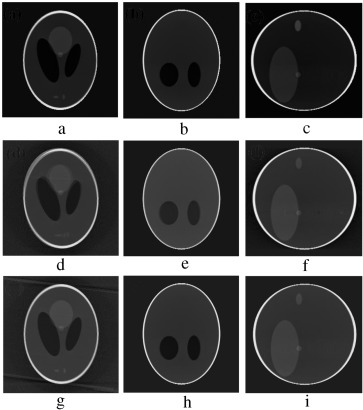

In order to validate the functionality of our proposed Marker-Based Motion Detection (MBMD) and artifacts mitigation technique (MB_FDK algorithm), we need to first simulate motion artifacts using our modified 3D Shepp–Logan phantom. For simulating motion artifacts, we need to perturb the 3D Shepp–Logan phantom during data acquisition time. Using the modified X-ray projection equation  [17] , which incorporated three translational Failed to parse (MathML with SVG or PNG fallback (recommended for modern browsers and accessibility tools): Invalid response ("Math extension cannot connect to Restbase.") from server "https://mathoid.scipedia.com/localhost/v1/":): {\textstyle (t_x,t_y,t_z)}

and three rotational (roll, pitch, yaw ) parameters of motion, we simulated several abrupt and gradual variations of motion on the 3D Shepp–Logan phantom. The cone-beam parameters listed in  Table 2  are used for our simulation. For abrupt variation of motion, we perturbed the 3D Shepp–Logan phantom with three different types of motion (translational, rotational, and rotational & translational combined) in three different test cases. Some of the images of motion corrupted projections and the axial, coronal and sagittal slices of the reconstructed volume of the above cases are plotted in  Figure 7 , Figure 8  and Figure 9 . For gradual variation of motion, we varied each parameter of motion separately in six different test cases. For gradual translational motion corruption cases, we gave ±6 mm of perturbation with a step size of ±1 mm. For gradual rotational motion corruption cases, we gave perturbation of ±5° with a step size of ±1°. The axial, coronal and sagittal slices of the gradual motion corrupted cases (+ perturbation only) are plotted in  Figure 10a  and Figure 10b .  Figure 10a  and Figure 10b  show the motion artifacts created in the reconstructed image due to the gradual perturbation given to the 3D Shepp–Logan phantom during data acquisition time. In Figure 10a , the 1st row shows the artifacts occurred due to the perturbation of +6 mm with a step size of +1 mm along the Failed to parse (MathML with SVG or PNG fallback (recommended for modern browsers and accessibility tools): Invalid response ("Math extension cannot connect to Restbase.") from server "https://mathoid.scipedia.com/localhost/v1/":): {\textstyle X}

-axis given. The 2nd and 3rd rows show the artifacts created due to the similar perturbation given to the phantom along the Failed to parse (MathML with SVG or PNG fallback (recommended for modern browsers and accessibility tools): Invalid response ("Math extension cannot connect to Restbase.") from server "https://mathoid.scipedia.com/localhost/v1/":): {\textstyle Y}

and Failed to parse (MathML with SVG or PNG fallback (recommended for modern browsers and accessibility tools): Invalid response ("Math extension cannot connect to Restbase.") from server "https://mathoid.scipedia.com/localhost/v1/":): {\textstyle Z}

axes, respectively. In Figure 10b , the 1st row shows the motion artifacts (artifacts dominant in the axial slice) occurred due to the rotational perturbation of 5° (clock-wise) with a step size of 1° given about the Failed to parse (MathML with SVG or PNG fallback (recommended for modern browsers and accessibility tools): Invalid response ("Math extension cannot connect to Restbase.") from server "https://mathoid.scipedia.com/localhost/v1/":): {\textstyle Z}

-axis (yaw). The 2nd row shows the motion artifacts (artifacts dominant in the sagittal slice) occurred due to the same rotational perturbation about the Failed to parse (MathML with SVG or PNG fallback (recommended for modern browsers and accessibility tools): Invalid response ("Math extension cannot connect to Restbase.") from server "https://mathoid.scipedia.com/localhost/v1/":): {\textstyle Y}

-axis (pitch). The 3rd row shows the artifacts (artifacts dominant in the coronal slice) occurred due to the rotational variation of similar motion about the Failed to parse (MathML with SVG or PNG fallback (recommended for modern browsers and accessibility tools): Invalid response ("Math extension cannot connect to Restbase.") from server "https://mathoid.scipedia.com/localhost/v1/":): {\textstyle X}

-axis (roll). From  Figure 7 , Figure 8 , Figure 9 , Figure 10a  and Figure 10b , it can be observed that head motion during data acquisition time resulted in doubling, ghosting, blurring and loss of resolution artifacts in the reconstructed images.

Motion artifacts occurred due to translational varaiation of gradual motion.

Figure 10a.

Motion artifacts occurred due to rotational varaiation of gradual motion.

Figure 10b.